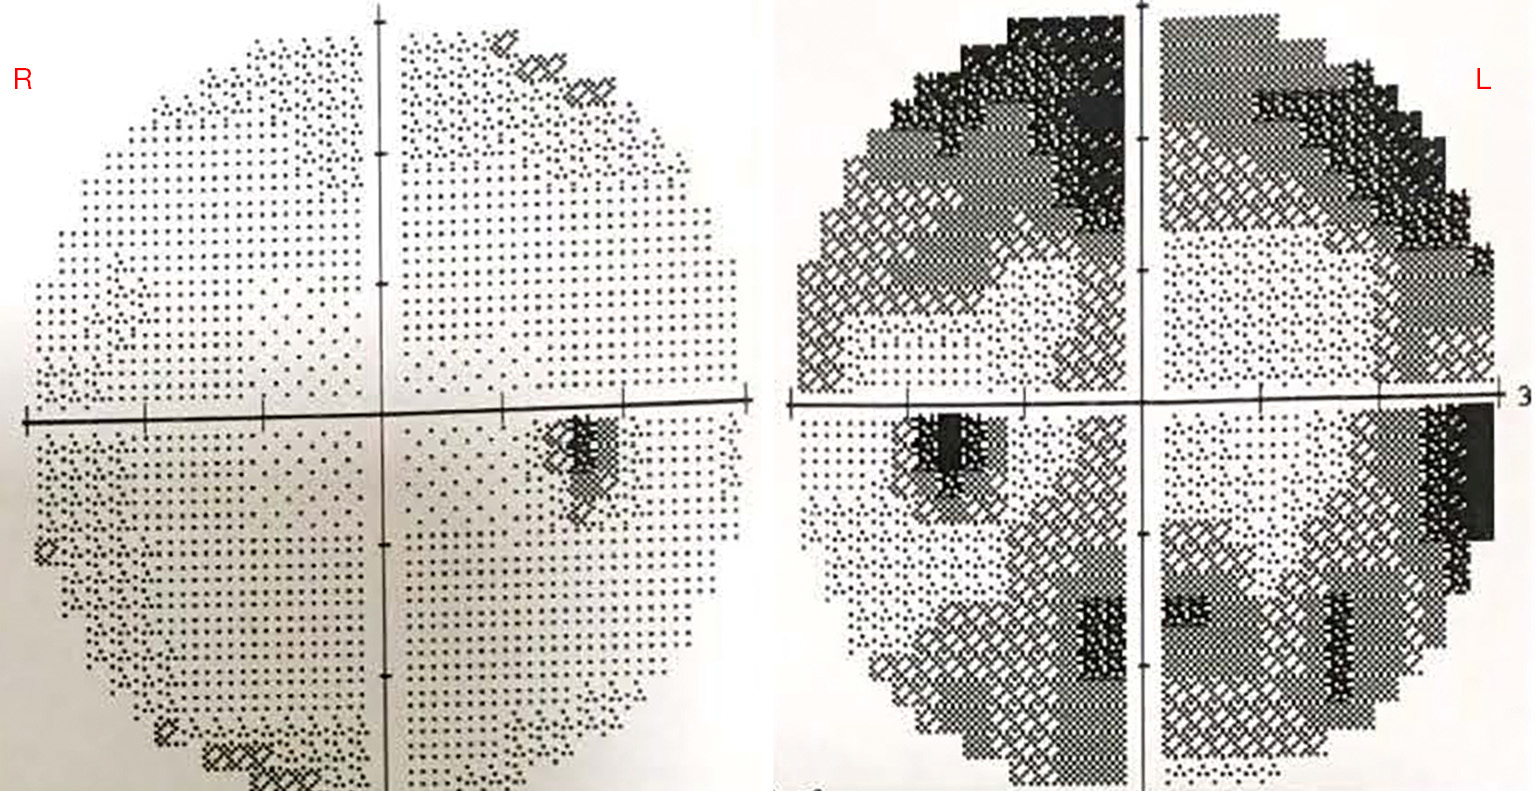

The exact mechanism for spontaneous resolution remains unknown but might involve continued postnatal maturation of the drainage angle (7). This makes the angle cope with the aqueous load leading to a reduction in IOP. Cupping reversal can be due to normalization of IOP in eyes with sufficient scleral elasticity that restores the diameter of the scleral canal (8). In this case, the cupping didn’t reverse. We still can see the cup to disc ratio of his LE is still stable compared to the first examination. Additionally, the visual field examination shows glaucomatous loss in accordance with the thinned RNFL (Figure 3).

figure3